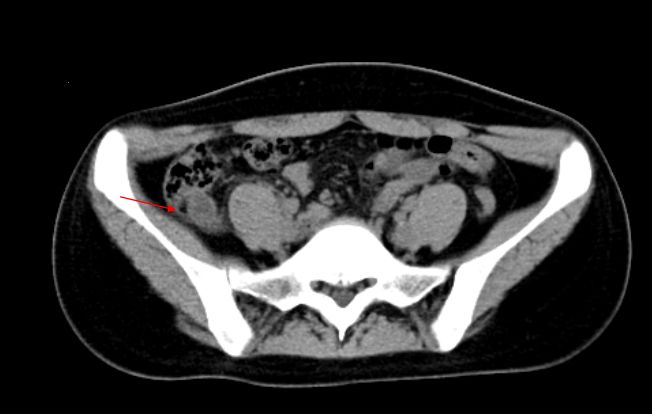

3)急性阑尾炎:是外科常见病,居各种急腹症的首位。其临床表现为转移性右下腹痛、恶心、呕吐,多数病人白细胞和中性粒细胞计数增高。右下腹阑尾区(麦氏点)压痛、反跳痛,是该病重要体征。

CT是其最具价值的影像检查手段。急性阑尾炎主要表现为阑尾增粗肿大,壁增厚,腔内积液积气和粪石,阑尾周围脂肪密度增高,少量积液,腹膜增厚。如出现肠腔外气体、肠腔外粪石及增强扫描阑尾壁缺损需诊断穿孔。

急性阑尾炎:CT平扫,阑尾增粗肿胀,腔内可见高密度粪石,阑尾浆膜面模糊,周围少许渗出。